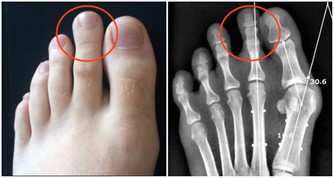

①一般來說,有身材偏胖、臉部較圓、臉上的肉比較虛、下頜窄、鼻子比例偏小等特徵的人易發生打呼;